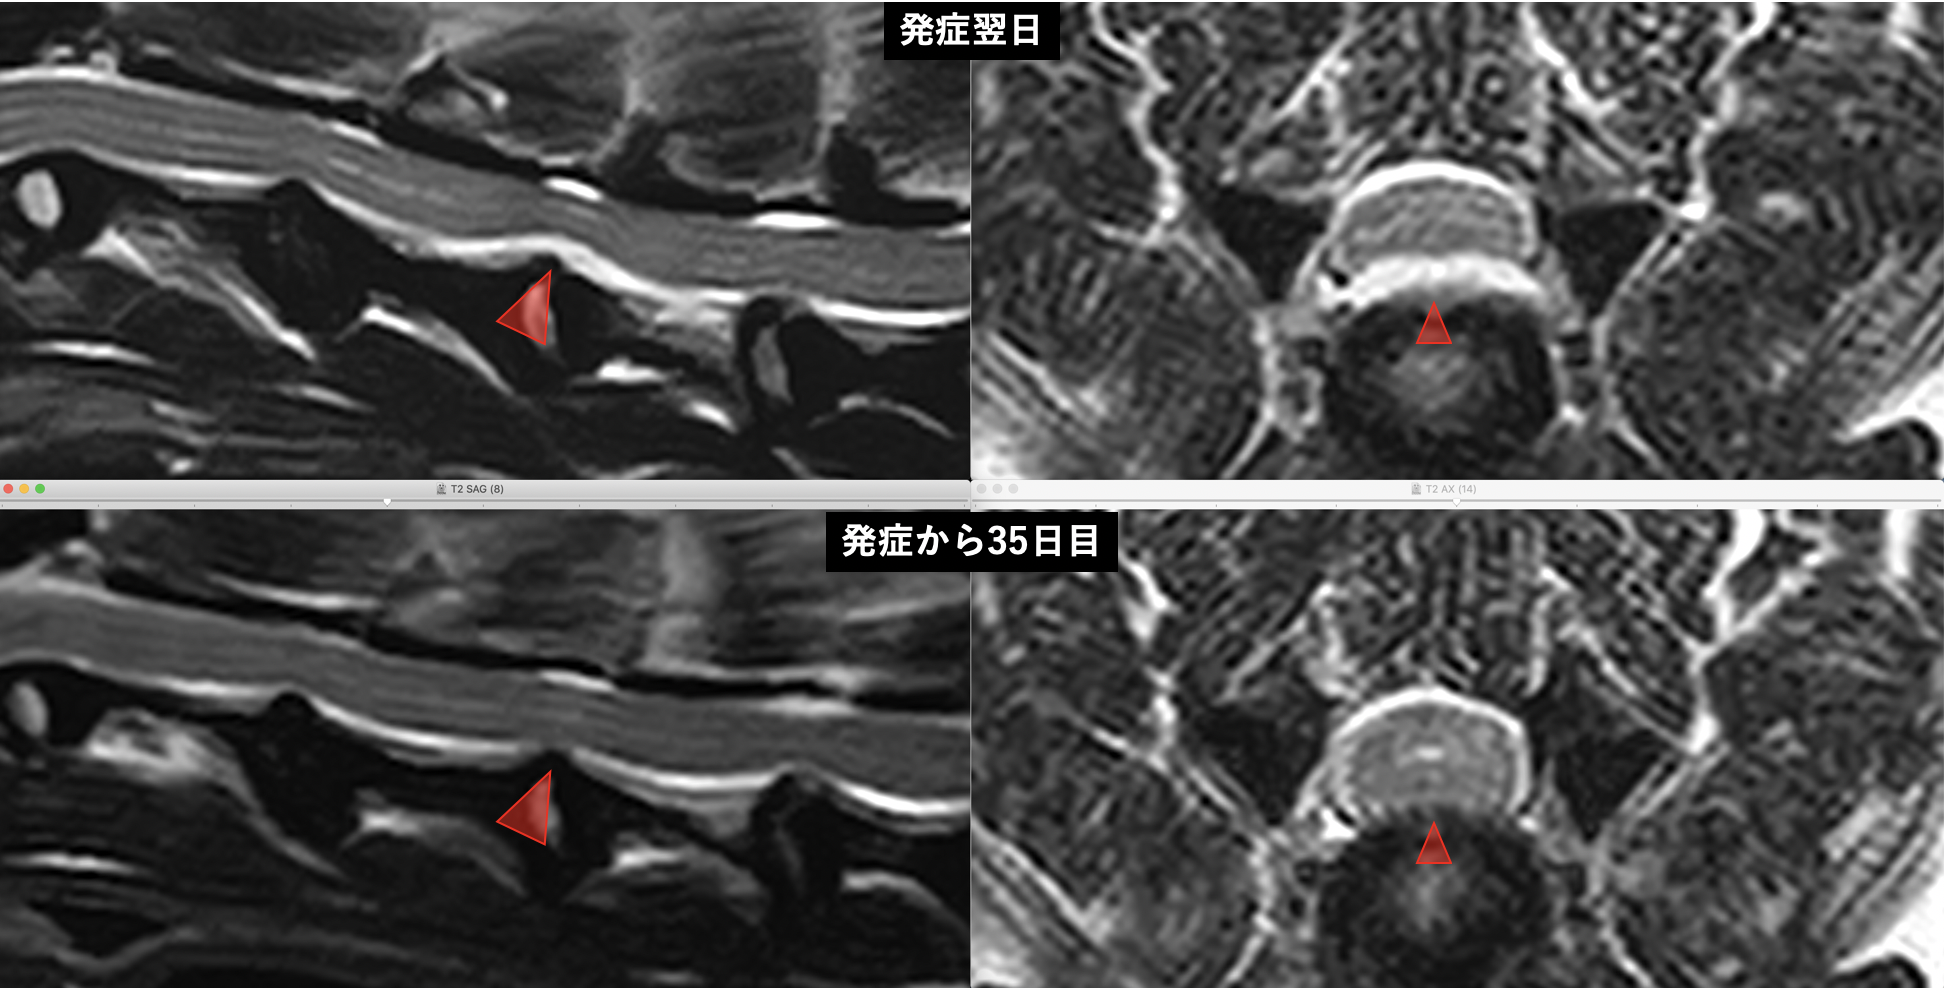

病変部位のMRI(T2WI横断):逸脱した水和髄核は白くカモメのような特徴的な形態を示す

上段が発症時/下段が発症後35日目のMRI:逸脱物質の消失と脊髄圧迫軽減が認められる